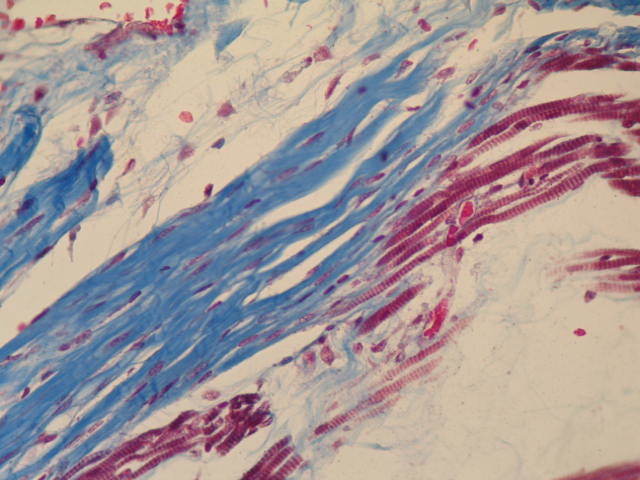

1. Tendón y músculo estriado esquelético: Se observa el tendón (tejido conectivo denso modelado) de color azul y el músculo estriado esquelético de color rojo oscuro. La coloración tricrómica sirve para visualizar las fibras colágenas.